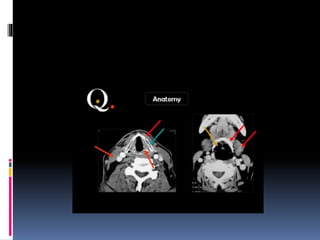

 Coronal sections of the nasopharynx show the-

eustachian tube opening, torus tubaris. Fossa of

rosenmuller and the adenoids, if present.

 Asymmetry of the Fossa of rosenmuller should

be looked for.